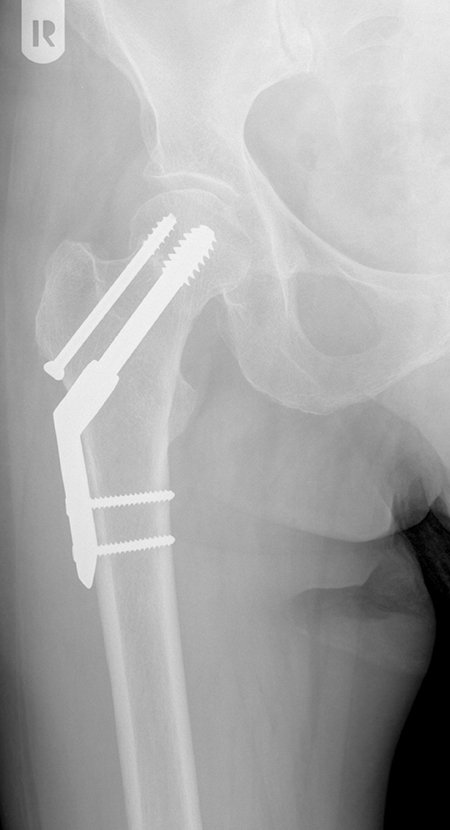

DIE FOLGENDEN BILDER ZEIGEN BEISPIELHAFT RÖNTGENERGEBNISSE NACH OPERATIVER BEHANDLUNG IN UNSERER ABTEILUNG:

Dynamische Hüftschraube und Antirotationsschraube bei stabilem Bruchtypus